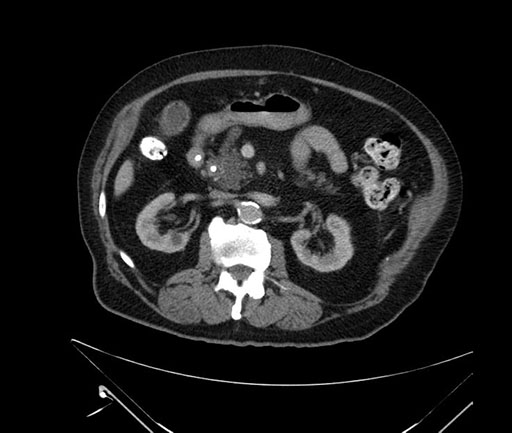

Imaging Analysis

Look through the patient's CT scan to identify any areas of concern for the necessary procedure.

Based on your CT findings, which issue(s) would give reason for "planned slowing down moment(s)" in this case?

Considering a standard Whipple procedure, what step(s) of the operation would you do differently in this case?